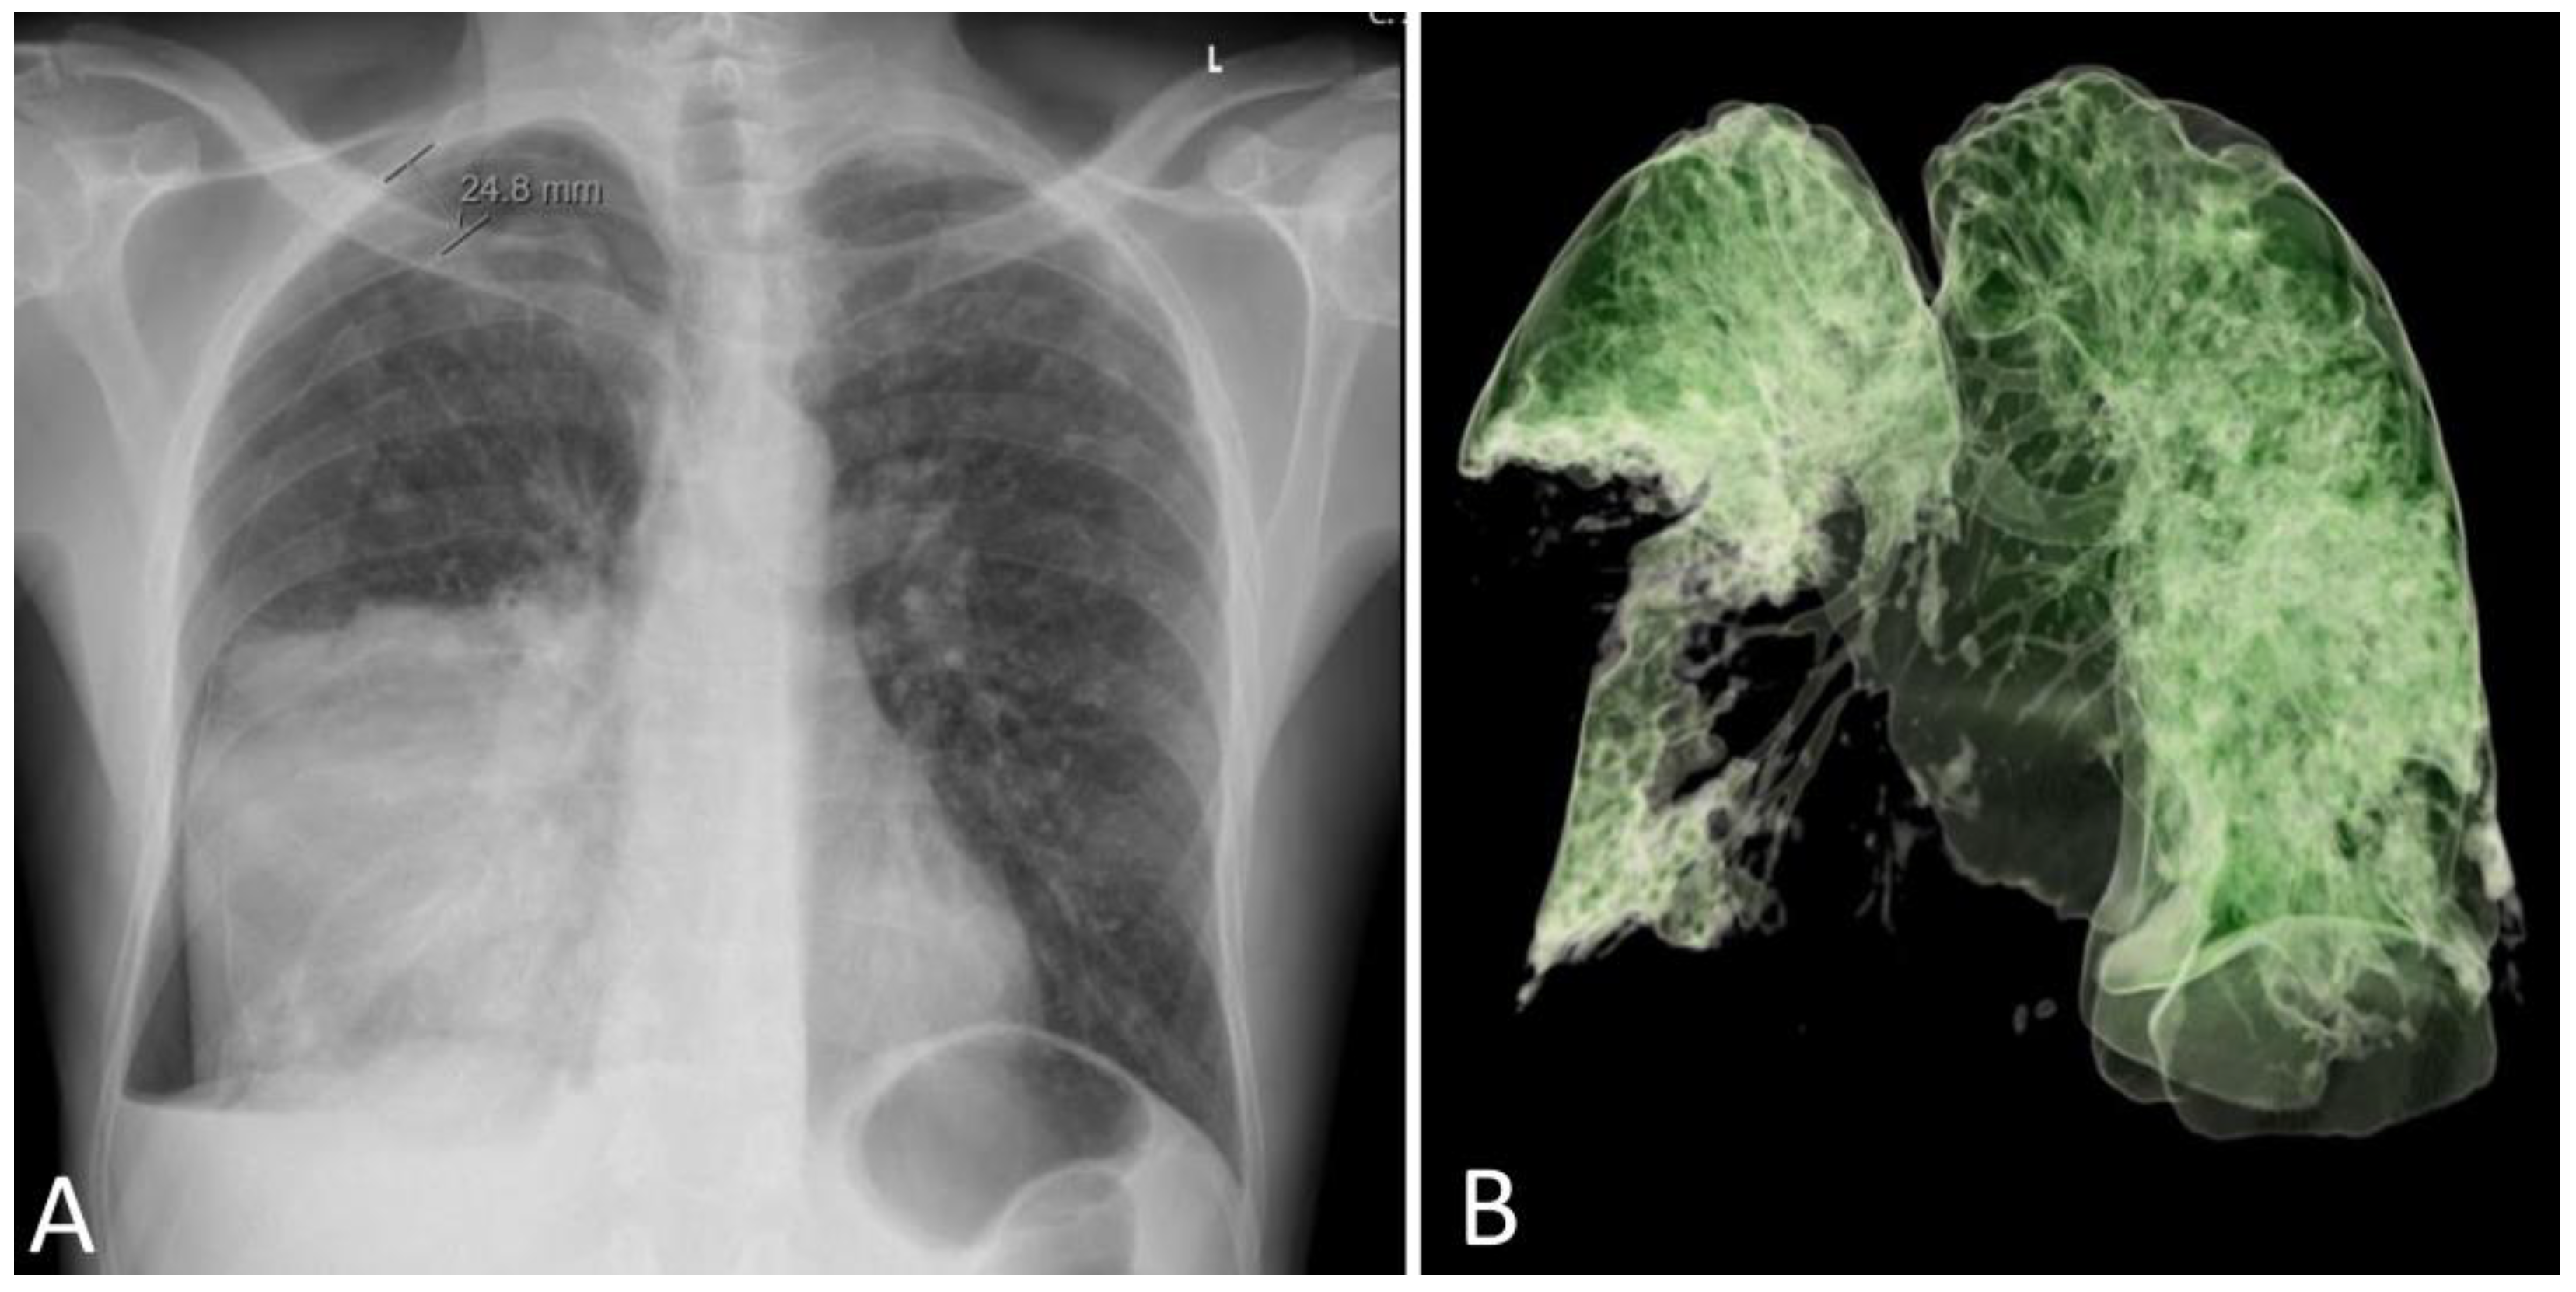

A 53–year–old male patient with no comorbidities or chronic therapy was admitted to the Intensive Care Unit due to severe respiratory failure. Five days before admission, the patient was hit by a metal object on the right side of the chest and complained of shortness of breath. Chest radiography revealed a right-sided pneumothorax and a thoracic drain was placed (Figure 1A).

Figure 1. Chest radiography on hospital admission with right-sided pneumothorax and a pulmonary infiltrate of the medial and lower lobe of the right lung (A). A complete absence of aeration of the lower and medial right lobe was present on day 3 (B).

On day 18, the patient was awake, conscious, oriented, and breathing spontaneously via face mask, and his SpO2 was 95%. The patient’s clinical status and chest radiograph both improved, and the thoracic drain was removed. The same day after the drain was removed, Sp02 decreased with silent breathing sounds apically on the right lung. Pneumothorax was suspected and confirmed after a chest radiograph. Re - thoracentesis was performed.

The patient's clinical condition improved in the following days, and he continued to breathe spontaneously with oxygenation. The control chest radiograph of the lung revealed complete expansion of the lung parenchyma with lung infiltrates on the medial and lower lung lobes. The patient's general condition gradually improved, and he was transferred to the ward on day 19 after ICU admission with supplemental oxygenation of 4 L O2/min via the nasal catheter and frequency of 18–20 breaths/minute with adequate oxygen saturation of 95–97%. The thoracic drain was removed on the ward (Figure 3).